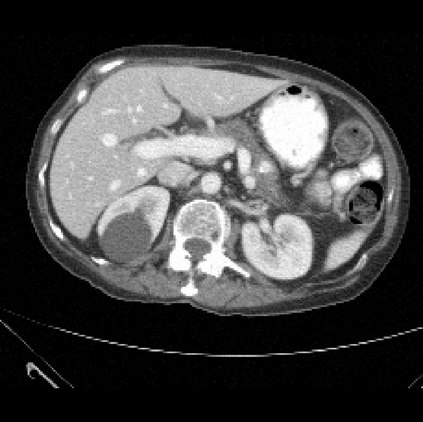

It is imperative to ensure the robustness of deep learning models in critical applications such as, healthcare. While recent advances in deep learning have improved the performance of volumetric medical image segmentation models, these models cannot be deployed for real-world applications immediately due to their vulnerability to adversarial attacks. We present a 3D frequency domain adversarial attack for volumetric medical image segmentation models and demonstrate its advantages over conventional input or voxel domain attacks. Using our proposed attack, we introduce a novel frequency domain adversarial training approach for optimizing a robust model against voxel and frequency domain attacks. Moreover, we propose frequency consistency loss to regulate our frequency domain adversarial training that achieves a better tradeoff between model's performance on clean and adversarial samples. Code is publicly available at https://github.com/asif-hanif/vafa.